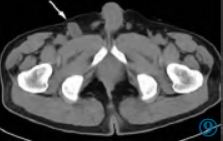

病例男,71 岁,8 年前因“排尿排便困难4 月,加重10天”首次入院。腹部CT 增强(图1~3)示直肠后方、骶前可见类圆形软组织肿块,大小约9.5 cm×8.6 cm×10.7 cm,边缘局部毛糙、邻近脂肪间隙模糊,密度欠均匀,平扫CT 值44 HU,增强扫描静脉期约50 HU,肿物强化不明显,肿物向前压迫直肠,部分层面与直肠右后壁分界欠清晰。术前诊断:直肠间质瘤。

图1~3 腹部CT 平扫轴位、静脉期轴位及矢状位图像示直肠后方、骶前类圆形软组织肿块。